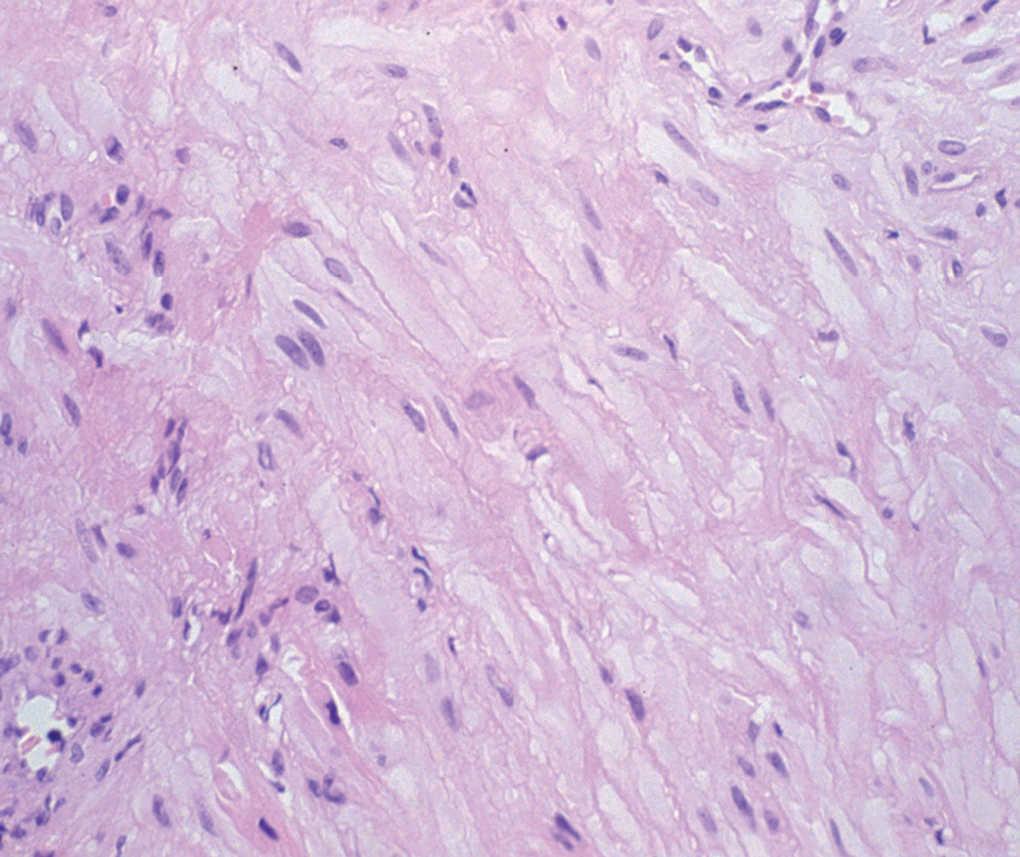

Se realizó una biopsia incisional en sacabocados que fue diagnóstica (fig. 2).

Fig. 2.--Imagen histopatológica en la que se observan múltiples haces de fibras de músculo liso. En el marco superior derecho se aprecia una estructura vascular de luz amplia y pared estrecha. Hematoxilina-eosina, x240.)

En el estudio histopatológico, tanto de la biopsia como de la resección completa, se observa la presencia de un tumor constituido por gruesos haces entrelazados de músculo liso rodeados de vasos (fig. 2). Estos vasos se caracterizaban por presentar luces amplias y cuyas paredes, pobres en tejido elástico, son difíciles de diferenciar de los haces de músculo liso. No se apreciaron estructuras adipocitarias ni de ningún otro tipo. Las tinciones inmunohistoquímicas confirmaron el origen del tumor; se tiñeron las células con vimentina y desmina, mientras que el HMB-45 fue negativo.

Hachisuga et al 7, tras analizar 562 angioleiomiomas, establecieron tres variantes histológicas principales: sólido o capilar, en los que densos haces de músculo liso rodean numerosos vasos de luz estrecha; cavernoso, caracterizado por unos vasos de luces amplias cuyas paredes son difíciles de distinguir de los haces de músculo liso intervascular, y el tipo venoso, en el que las gruesas paredes vasculares son perfectamente distinguibles de los haces de músculo liso. Con posterioridad se han descrito otras dos variantes: un subtipo epitelioide 9, compuesto por células de núcleo ovalado y citoplasma eosinófilo, y un subtipo pleomórfico, con marcado pleomorfismo celular pero con ausencia de mitosis 10.